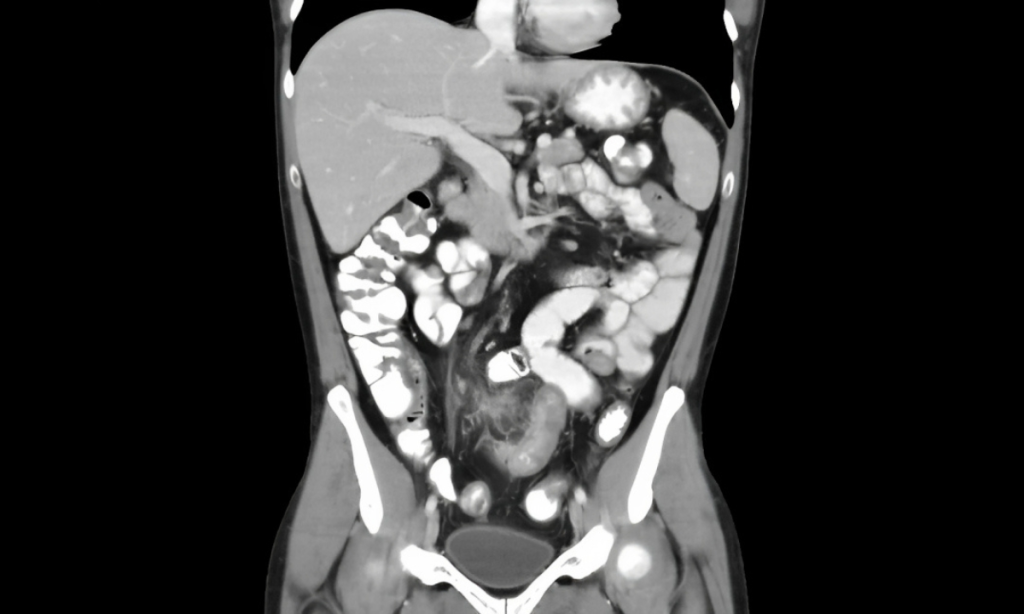

CT (Computed Tomography) Abdomen Scan एक advanced imaging test है जो पेट के अंदर के organs की cross-sectional images देता है।

यह test खासतौर पर इन स्थितियों में उपयोगी है:

- लगातार पेट दर्द

- Liver या Kidney disease

- Tumor या cancer suspicion

- Internal injury या infection

👉 Ultrasound से ज्यादा detailed और MRI से सस्ता होने के कारण CT scan बहुत common हो गया है।